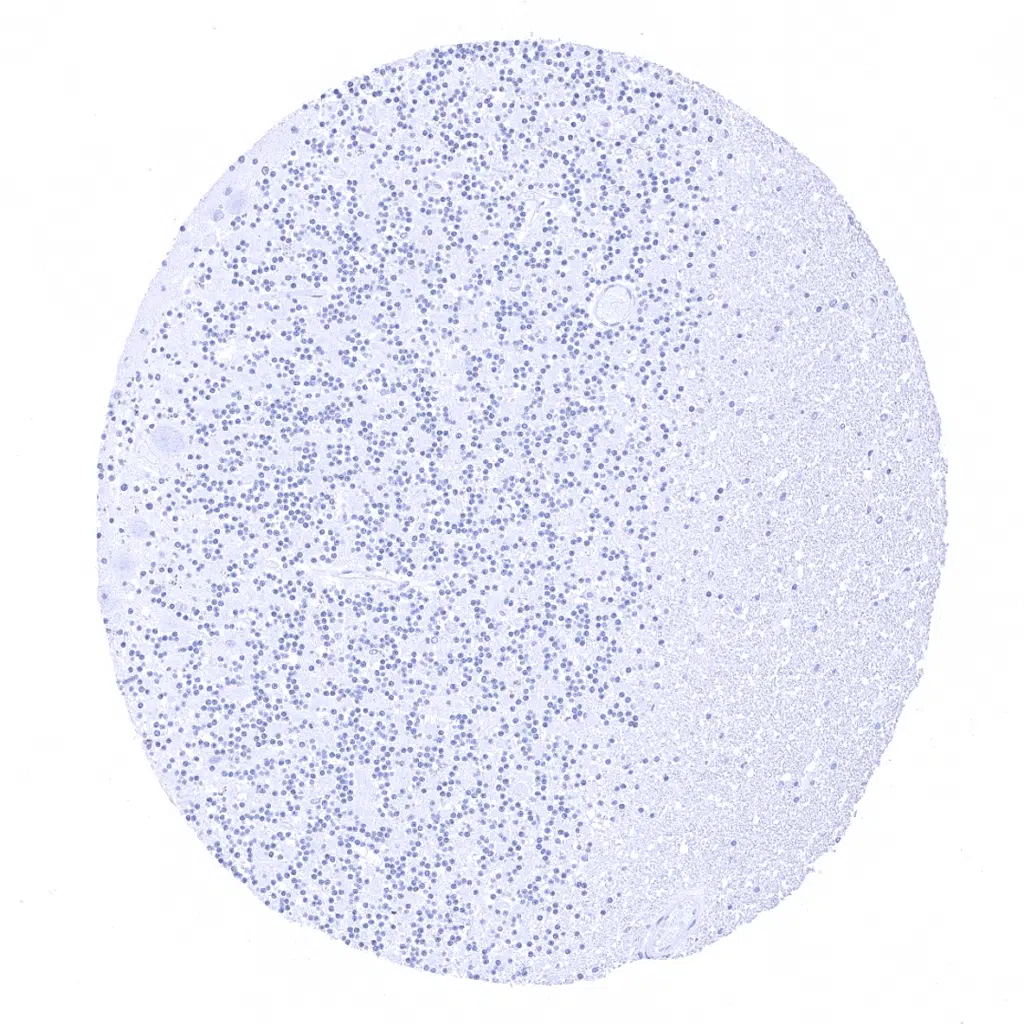

Lymph node